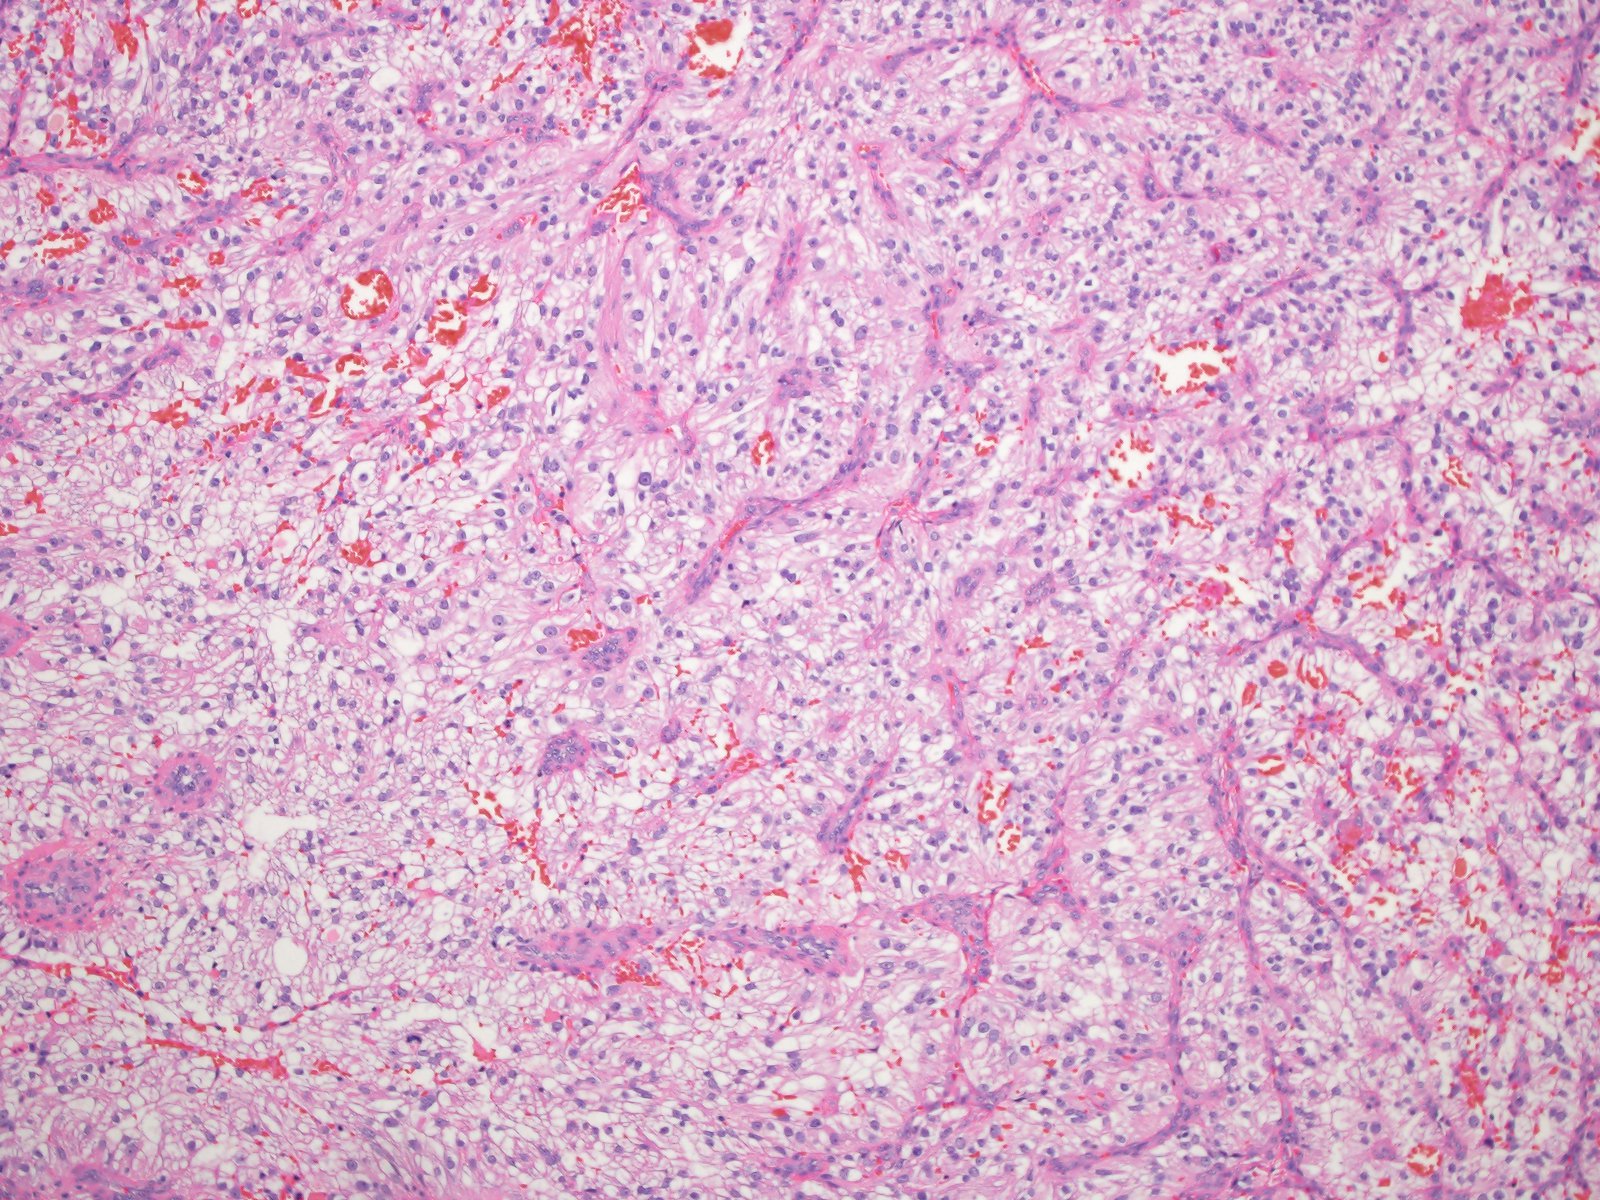

Classification of renal tumors

Case ID: 1059